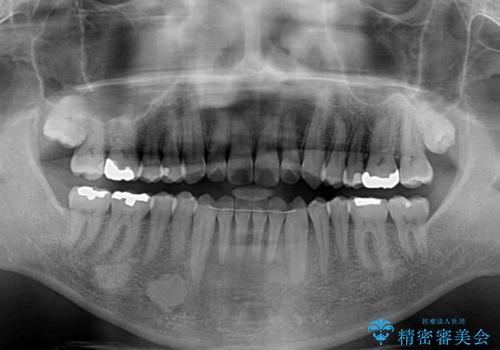

- 前歯のデコボコとクロスバイトを気にして来院された患者様です。

40代半ばであり、あまり周りに気を遣われずに治療を進めたいとのことで、インビザラインにて矯正治療を行うこととしました。

毎日22時間の装着時間をきっちりと守ってくださり、1年半かけずに思い通りの歯列に仕上げることができました。